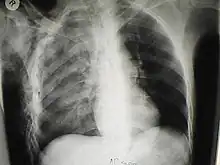

Chest X-ray is the most common method used for diagnosis,[37] and may be used to confirm a diagnosis already made using clinical signs.[20] Consolidated areas appear white on an X-ray film.[42] Contusion is not typically restricted by the anatomical boundaries of the lobes or segments of the lung.[27][43][44] The X-ray appearance of pulmonary contusion is similar to that of aspiration,[32] and the presence of hemothorax or pneumothorax may obscure the contusion on a radiograph.[25] Signs of contusion that progress after 48 hours post-injury are likely to be actually due to aspiration, pneumonia, or ARDS.[10]

Although chest radiography is an important part of the diagnosis, it is often not sensitive enough to detect the condition early after the injury.[35] In a third of cases, pulmonary contusion is not visible on the first chest radiograph performed.[7] It takes an average of six hours for the characteristic white regions to show up on a chest X-ray, and the contusion may not become apparent for 48 hours.[7][27][43] When a pulmonary contusion is apparent in an X-ray, it suggests that the trauma to the chest was severe and that a CT scan might reveal other injuries that were missed with X-ray.[2]